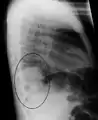

A chest X-ray showing a very prominent wedge-shape bacterial pneumonia in the right lung